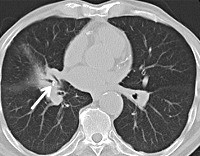

• Тесты на облучение легких. Желчнокаменную болезнь трудно обнаружить на рентгенограмме грудной клетки. Косвенными симптомами заболевания являются ателектаз сегмента или доли, сегмент линейного фиброза, наличие единичных или множественных окаменелых лимфатических узлов в области корней легких. Динамическое рентгенологическое исследование может определить исчезновение одной или нескольких кальцификаций. Сам бронх хорошо визуализируется при бронхографии и КТ дыхательной системы.